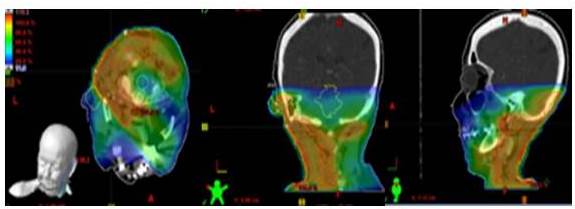

Al grupo de pacientes con diagnóstico de sarcomas de cabeza y cuello pertenecieron 25 individuos, predominando aquellos en la cuarta década de la vida. No hubo diferencia importante en cuanto al sexo. La histología más frecuente fueron los angiosarcomas seguidos de los dermatofibrosarcoma, los cuales no se incluyen en la clasificación de la AJCC 2017; los 6 pacientes restantes (24 %) se catalogaron como T3N0M0 y T2N0M0. Solo 4 pacientes no fueron sometidos a cirugía, de aquellos sometidos a cirugía (21), 6 ameritaron más de 2 cirugías antes de la radioterapia. En más de la mitad (11) se obtuvieron márgenes quirúrgicos negativos. Solo 5 recibieron tratamiento sistémico en sus distintas modalidades y la radioterapia se realizó de forma posoperatoria en la gran mayoría (21 pacientes). La técnica de planificación más empleada fue la conformada tridimensional, seguido de la convencional (2D) y luego la combinación de las anteriores con uso de electrones. La dosis total promedio administrada fue 6 400cGy (Cuadro 2 y Figura 1).

Las complicaciones agudas más resaltantes en este grupo fueron la dermatitis grado II (52 %), seguido de la mucositis grado II (24 %) y mucositis grado I (20 %) (Cuadro 3)

En cuanto a las toxicidades crónicas, la fibrosis en piel grado I y II fue reportada sólo en 9 pacientes (Cuadro 3).

Al momento del estudio el 64 % de los pacientes se encontraban vivos sin enfermedad, sólo 5 pacientes murieron a causa de la enfermedad, el resto (4 pacientes) continúan vivos con enfermedad (Cuadro 4).

El tiempo promedio de seguimiento fue de 32,4 meses y la mediana 15 meses. La supervivencia libre de enfermedad fue de 44,9 %. La supervivencia global se reportó en 59,8 % (Figura 2).